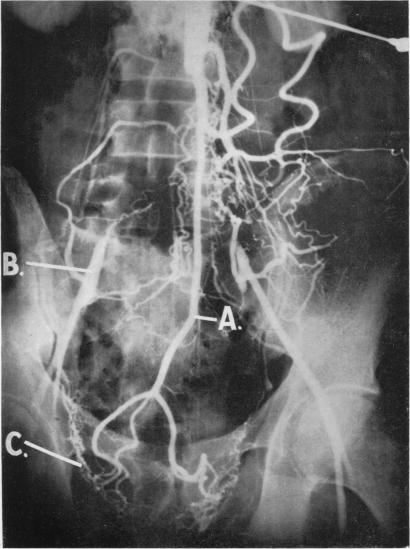

Surgical anatomy of the blood supply of the distal colon.